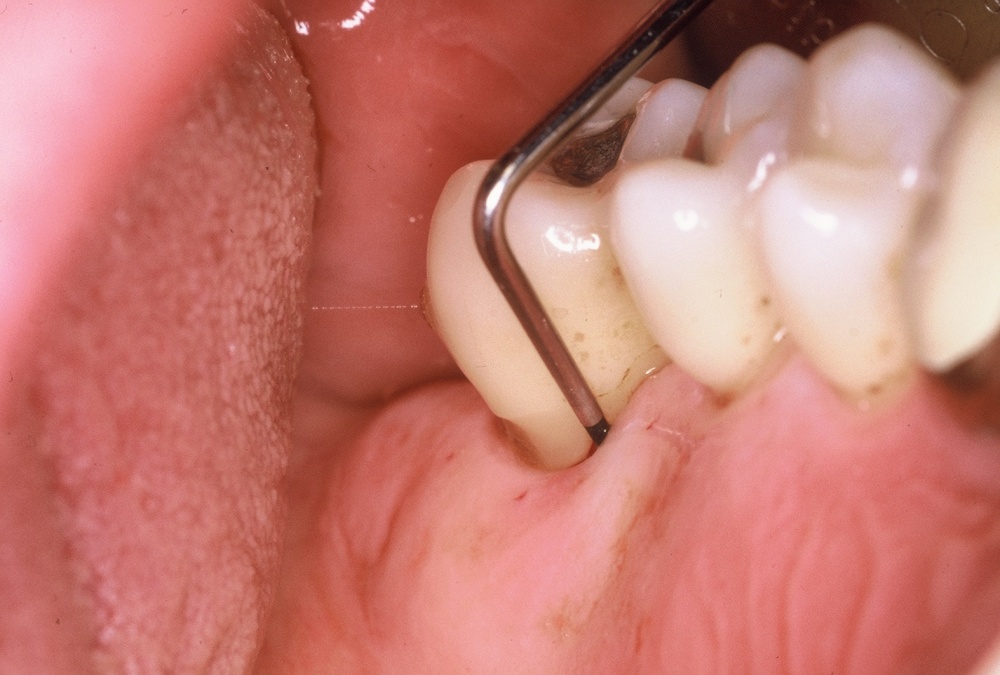

•IP1 – Mundhygienestatus: Darunter versteht man die Beurteilung der Mundhygiene mittels Anfärben der bakteriellen Beläge und der Benutzung eines geeigneten Index, z. B. des Approximalraumplaqueindex (Abb. 6). Für die Beurteilung des Gingivazustandes ist ebenfalls ein geeigneter Index anzuwenden, z. B. der Sulkusblutungsindex.

Im Regelfall werden die individualprophylaktischen Maßnahmen im Rahmen einer einsatzvorbereitenden Prophylaxesitzung durchgeführt. Die Besonderheiten des Einsatzes können Auswirkungen auf das individuelle Mundhygieneverhalten der Soldaten/innen haben, sodass die Durchführung der beschriebenen Maßnahmen im zeitlichen Zusammenhang zum bevorstehenden Einsatz sinnvoll ist. In Abhängigkeit von den jeweiligen klinischen Befunden kann die Entfernung harter und weicher Beläge in dieser Sitzung indiziert sein (Abb. 7). Die Entscheidung darüber trifft jeweils der SanOffz/Zahnarzt.